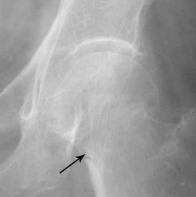

Avulsion Fracture

<div id="article-content-body"><p><img src="http://imaging.cmpmedica.com/consultantlive/images/articles/2006/09012006/0609Con1PESporAF1_thumbnail.jpg" style="float:...